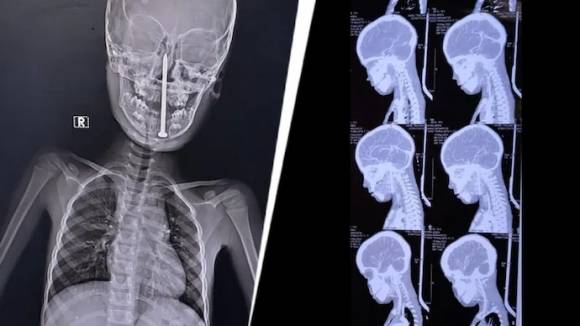

인도에서 한 아이가 놀다가 넘어지면서 8㎝ 길이의 못이 뇌까지 박히는 중상을 입었으나 10시간의 대수술 끝에 기적적으로 생존했다.

소년은 놀다가 실수로 넘어지면서 쇠못이 목을 통해 뇌까지 박히고 말았다. 사고 직후 인근 병원으로 긴급 이송됐지만 상태가 심각해 곧바로 KGMU로 옮겨졌다.

의료진은 MRI와 CT 검사 결과를 분석한 뒤 매우 위험한 상황임을 확인하고 신경외과, 이비인후과, 마취과, 외상외과, 소아과 등과 협력해 수술에 나섰다. 최첨단 미세 수술 기법 등을 동원한 의료진은 뇌와 주요 혈관 손상 없이 못을 제거하는 데 성공했다.